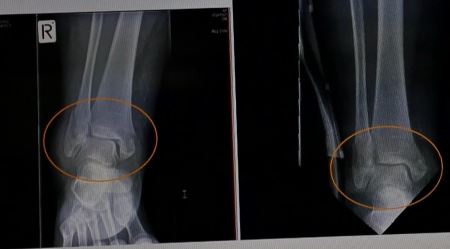

2015 年 11月,王久春在漢米爾頓市遭遇嚴重車禍,檢查確認膝蓋、腳後、雙腳踝骨等多處粉碎性骨折。醫院專家組醫生告知要立即手術,否則會殘廢或有生命危險。可她不願身體中被嵌入數塊最長8吋的鋼板,更不願意在醫院裏躺上一年半載,她知道即使那樣,也不能完全保證她能像以往一樣行走自如。她心裏確信法輪功能讓自己恢復正常。於是,她拒絕了手術,並在律師幫助下與醫院簽署免責協議,回了家。當時她全身腫痛,生活完全不能自理。

王久春說,「回家後,憑著對法輪大法的堅定信念,堅持通讀《轉法輪》,聽煉功音樂,把心靜下來,不斷找自己在修煉過程中所存在的問題(不足)。」三周後的兩次複查中,醫生驚奇的發現,骨折明確癒合趨向。三個月後再去檢查,醫生說恢復得非常好,不用再來了。次年5月13日,她還坐飛機從紐西蘭飛到美國紐約,參加「世界法輪大法日」的慶祝活動。主任醫師說,「病人沒有接受正規的外科治療的情況下,僅半年時閒,恢復良好,行走如初,那我們可以認為是一個醫學上的奇蹟了。」